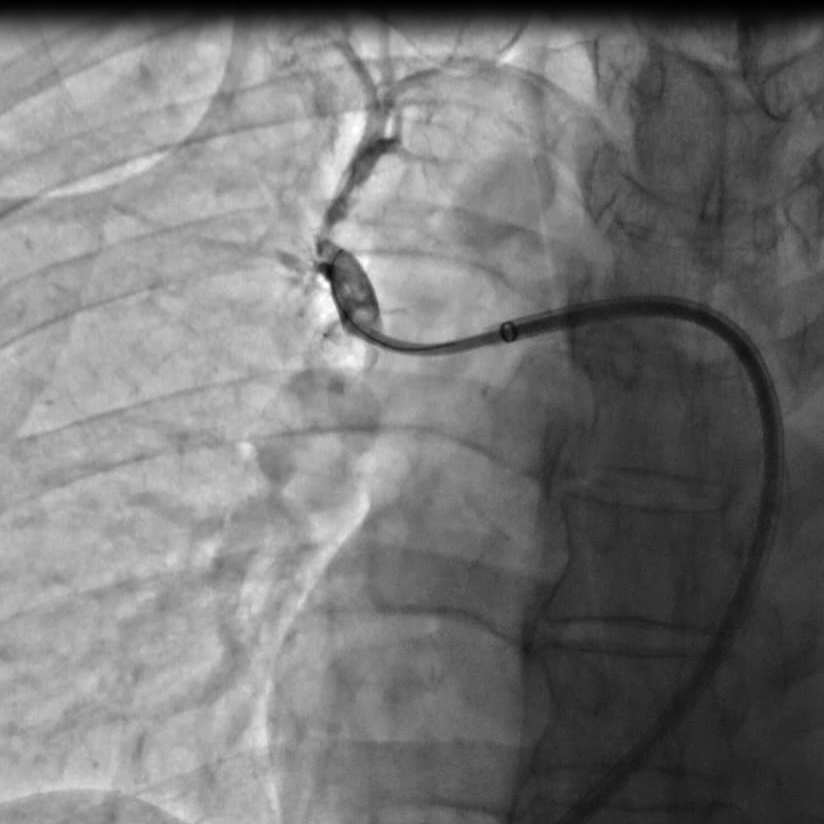

囊扩张术后狭窄改善的影像

手术由心脏中心主任马翔、副主任医师吕文魁及戴远辉完成,团队分别依次对患者右肺动脉A10段、A5段、A1段行球囊扩张,先用2.0mm的球囊以6—12atm扩张,再使用3.0mm的球囊逐级扩张,球囊扩张后患者胸闷症状即刻好转,术后8小时已下地行走,目前各方面生理指标达到预期,即将出院。